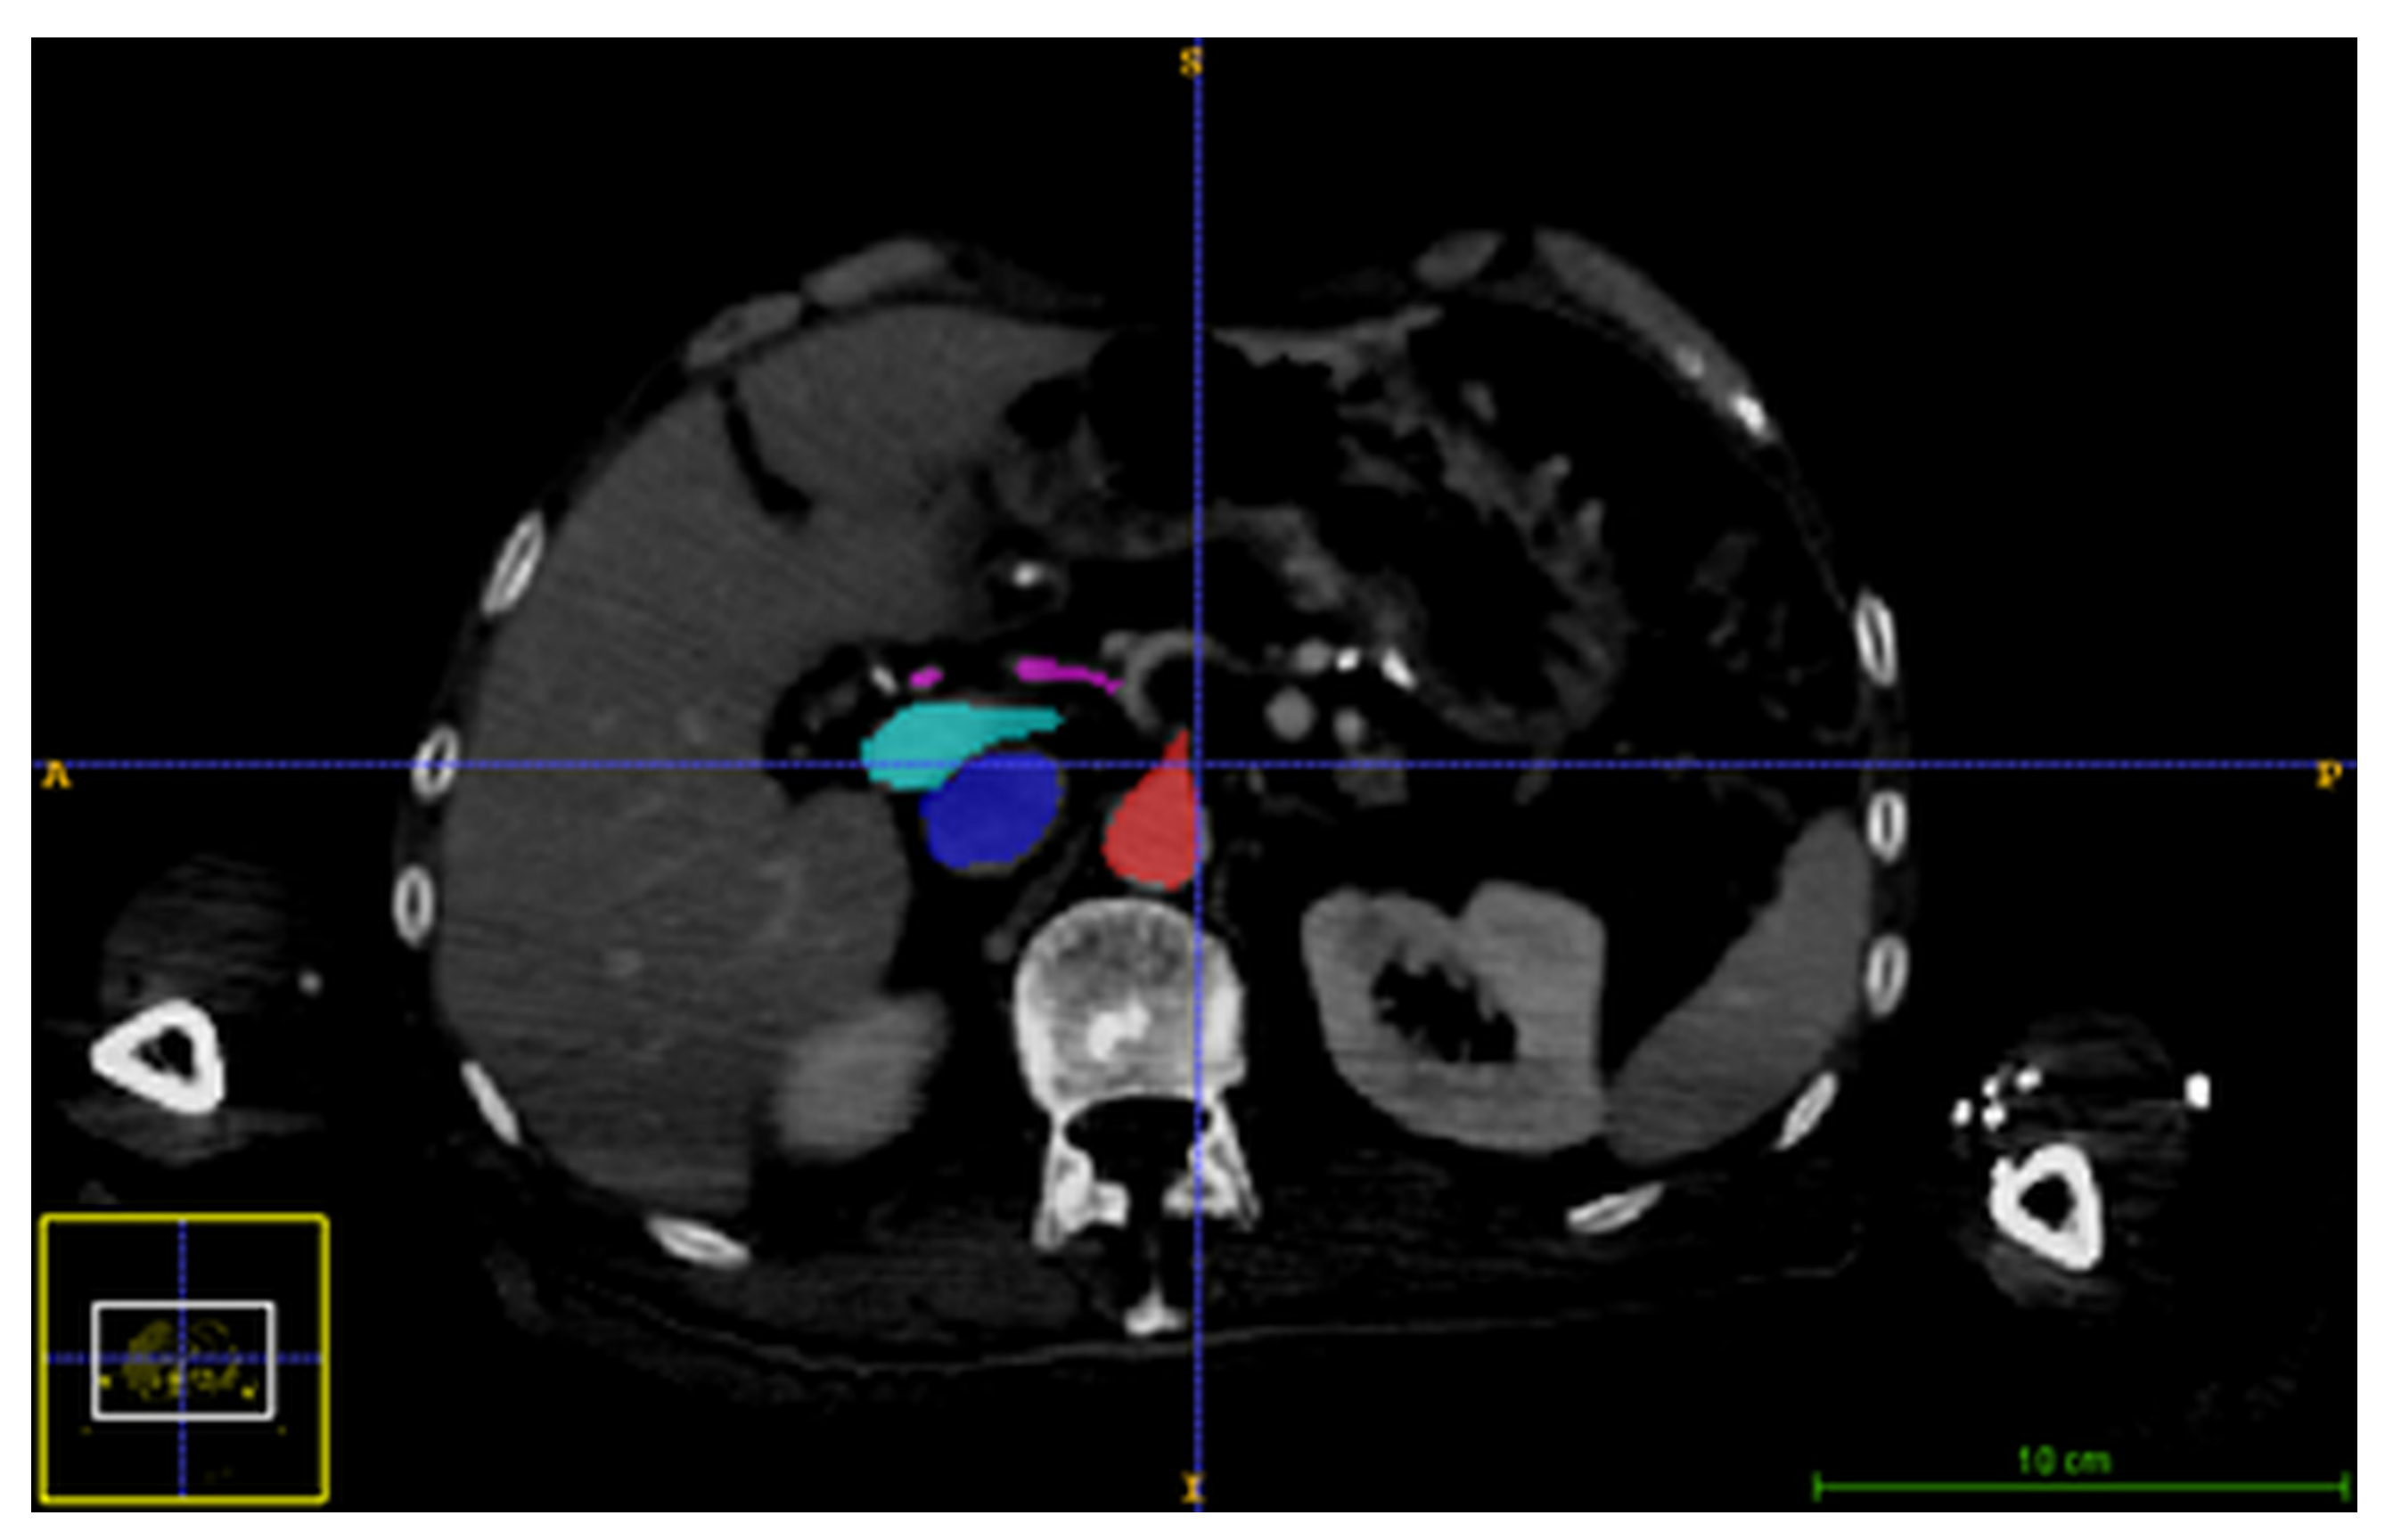

2.2.1. Image Acquisition

2.2.3. Determining the Spatio-Temporal Correspondence between the Intraoperative US Sequence and Pre-Operative the 4D CT Images